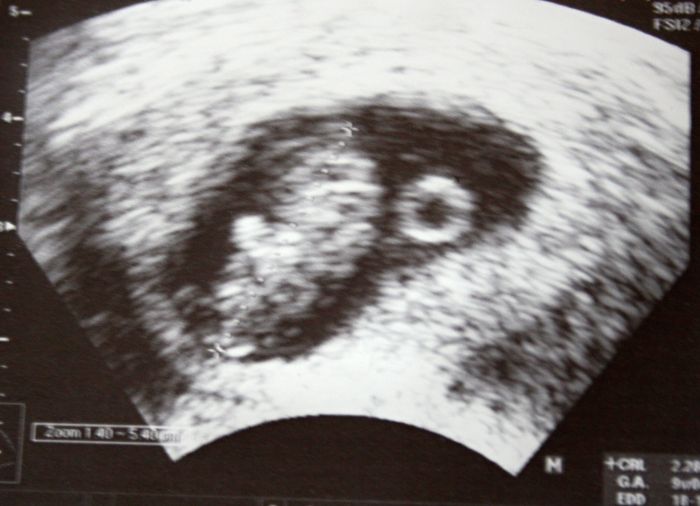

A máš tu krásnou fotečku drobka

Zkusím ji sem taky vložit

Marse, ty jo, to je už úplné miminko